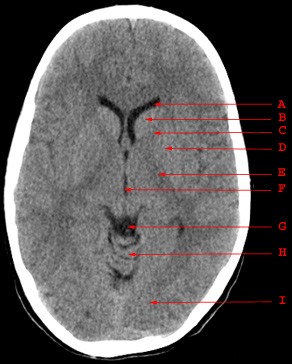

Head CT > Anatomy > Normal Anatomy 5

Normal Anatomy

A. Anterior Horn of the Lateral Ventricle

B. Caudate Nucleus

C. Anterior Limb of the Internal Capsule

D. Putamen and Globus Pallidus

E. Posterior Limb of the Internal Capsule

F. Third Ventricle

G. Quadrigeminal Plate Cistern

H. Cerebellar Vermis

I. Occipital Lobe